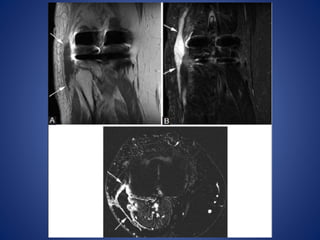

• #9 PTFJ cyst. Axial T1W MR image (A) demonstrates uniformly hypointense mass (arrow) with small tail (arrowhead), arising from proximal tibiofibular joint. Lesion (arrow) is hyperintense on STIR (B) and does not enhance on post-contrast T1W fat-saturated image

• #10 PTFJ cyst. A 57-year-old man with foot drop. Axial (PD) image (A) shows large cyst (arrows) compressing the common peroneal nerve (arrowhead). There is muscle edema (arrow) in anterior tibialis on the axial STIR image (B)